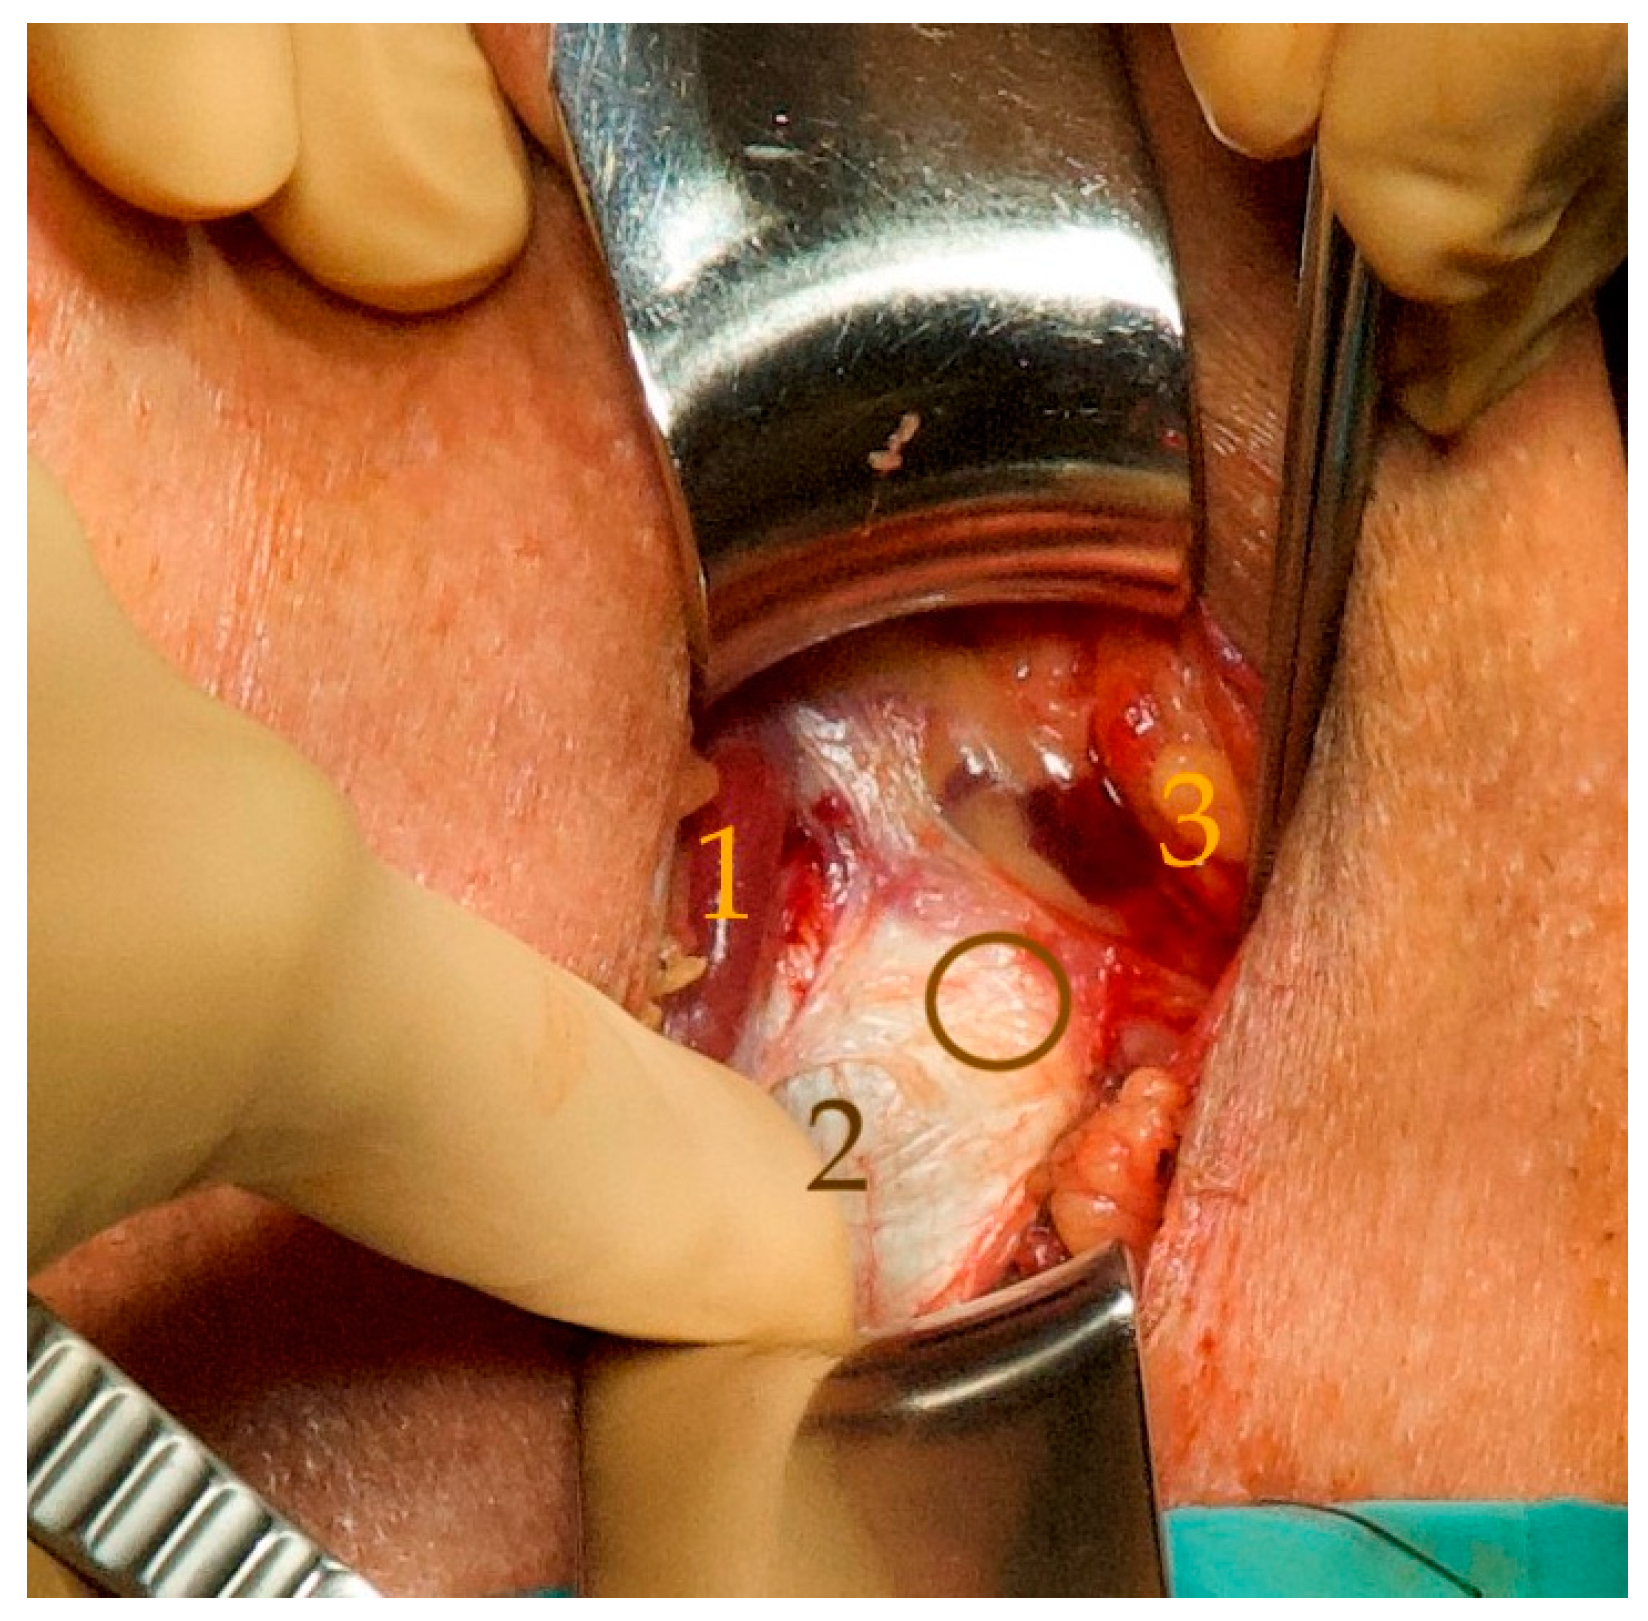

- The perineal central tendon was transected transversely on the bulbospongiosus muscle to allow a partial retrobulbar position of the silicone pad (Figure 2);